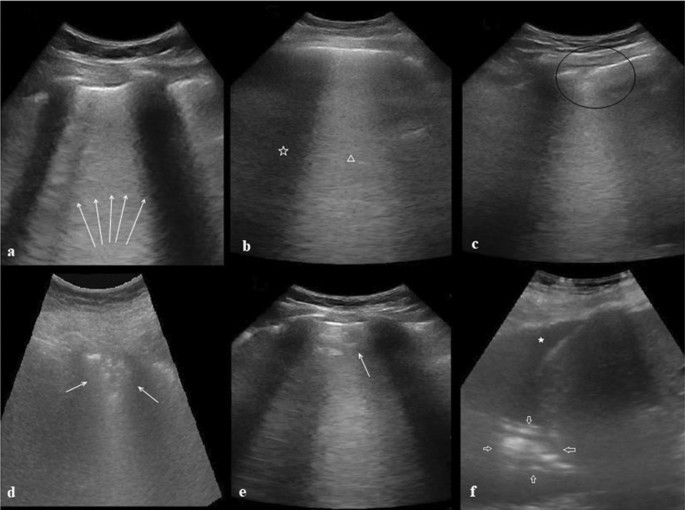

Fig. 2

figure 2

LUS images of COVID-19-related pneumonia. a White arrows: diffuse B lines, b white star: lesion-free zone, white triangle: B lines (on–off effect), c black circle: irregular pleural line, d white arrows: sub-pleural consolidation, e white arrow: halo sign (Fig. 1, same patient), f white star: pleural effusion, white arrows: consolidations